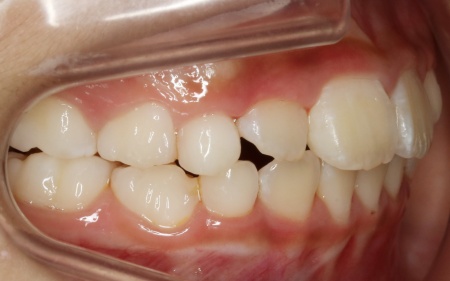

治療後

治療中は、スクリューを少しずつ回すことで顎の骨が徐々に横方向に拡大されていき、永久歯が生えるためのスペースを十分に確保することができました。

拡大治療が完了したあとは、顎の状態を安定させるためのリテーナー(保定装置)を装着し、治療を終了しています。